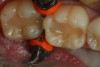

Figure 2. Bulk fill Flowable composite (X-tra Base: VOCO America) has been placed as a dentin replacement in a 4 mm increment after using a self etching adhesive to bond the flowable to the surface of the dentin.

Figure 2

In 2010, bulk fill flowable composites were introduced to the dental marketplace, the first being Surefil SDR (Smart Dentin Replacement) by DENTSPLY Caulk. Since then, many other bulk fill flowable composites have followed (Xtra Base, VOCO America; Venus Bulk Flow, Heraeus Kulzer; HyperFil DC, Parkell; Beautifil Bulk Flowable, Shofu; Filtek Bulk Fill, 3M ESPE). These materials are indicated for use as a bulk fill base (dentin replacement) beneath posterior composite restorations and can be placed in a single increment up to 4 mm in depth (Figure 2). Being able to place that amount of material in a single increment is a significant time saver, and while the concept sounds quite simple, there are several important requirements a material must meet for this particular indication. According to the manufacturers, these include 1) increased depth of cure; 2) a viscosity that will readily adapt to the internal walls of the cavity without the need for manipulation of the material; and 3) low polymerization shrinkage stress.12-15